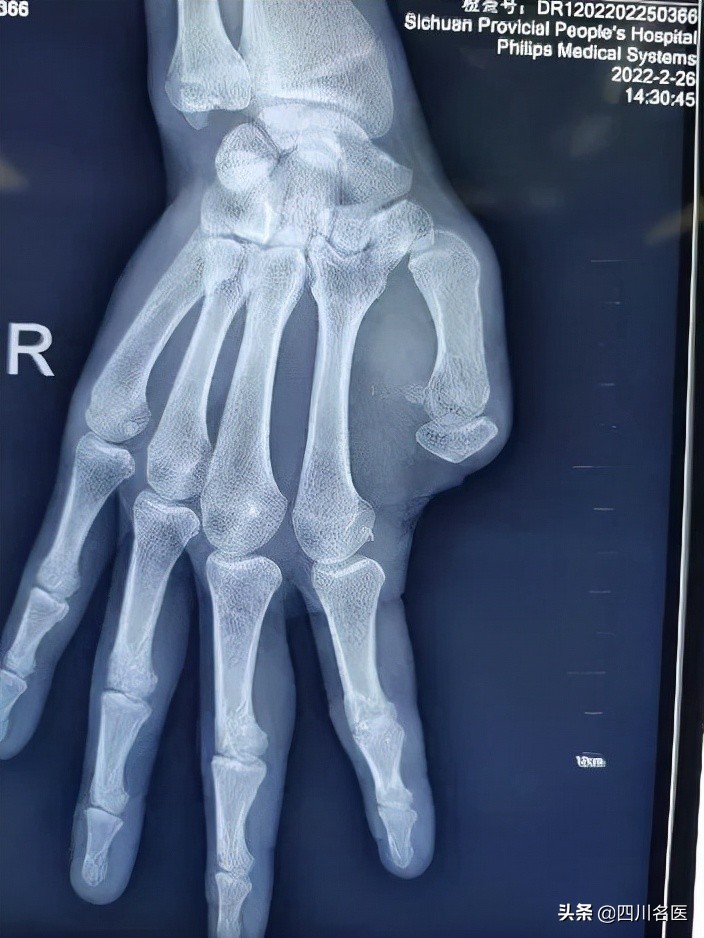

22岁小伙小杨, 右拇指因电锯伤缺失10多年。

右手拇指缺失,让小伙子读书、吃饭、写字等日常生活活动都会受到影响。

据四川省人民医院骨科主治医师肖成伟博士介绍:“大拇指在手的功能中发挥着至关重要的作用,如握、对捏和对指等常规动作都离不开它。 没了大拇指,40-50%的手功能将丧失。 ”